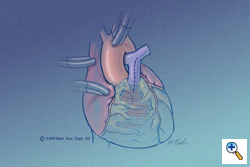

Pulmonary Artery Incision

The patient has been placed on cardiopulmonary bypass with aortic and bicaval venous cannulation. The dotted line indicates the vertical incision to be made in the main pulmonary artery. Through this incision the pulmonary valve and annulus can be inspected. If possible, a pulmonary valvotomy can be performed and the annulus measured with dilators. In patients with moderate to severe hypoplasia of the annulus (generally more than 1 mm smaller than a -1 Z value), a transannular repair can be performed with the use of the monocusp. The other indication for the use of the monocusp would be a post-repair RVOT gradient greater than 25-30 mmHg following a valve-sparing attempt. This portion of the operation can be performed after the ventricular septal defect (dotted line circle) has been closed and the aortic cross clamp removed.

The patient has been placed on cardiopulmonary bypass with aortic and bicaval venous cannulation. The dotted line indicates the vertical incision to be made in the main pulmonary artery. Through this incision the pulmonary valve and annulus can be inspected. If possible, a pulmonary valvotomy can be performed and the annulus measured with dilators. In patients with moderate to severe hypoplasia of the annulus (generally more than 1 mm smaller than a -1 Z value), a transannular repair can be performed with the use of the monocusp. The other indication for the use of the monocusp would be a post-repair RVOT gradient greater than 25-30 mmHg following a valve-sparing attempt. This portion of the operation can be performed after the ventricular septal defect (dotted line circle) has been closed and the aortic cross clamp removed.